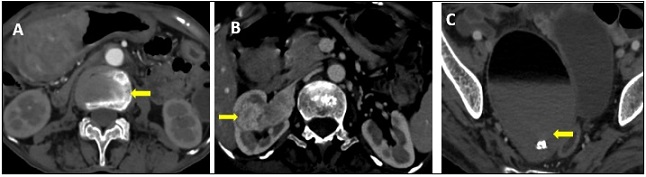

Synchronous multiple primary malignancies are rare clinical condition, and the occurrence of triple synchronous primary tumors are exceptionally uncommon. Among these, the simultaneous occurrence of primary gastric, renal, and ovarian tumor has seldom been reported in the literature. We present a case of a 70 year- female who presented with abdominal pain and endoscopic biopsy showed gastric adenocarcinoma. CECT abdomen and pelvis subsequently revealed an incidental right renal and ovarian tumor. The patient underwent curative surgical resection for all three tumors in a single operative session. Post-surgical histopathology confirmed Clear cell renal cell carcinoma and Ovarian mature cystic teratoma. There was no evidence of metastasis among the tumors. Elderly patient with gastric carcinoma have a higher risk of developing a synchronous tumor than younger people. This case highlights the importance of thorough diagnostic evaluation of multiple primary malignancies in an elderly patients with gastric cancer , as the differentiation between metastatsis and synchronous primaries significantly influences the planning of treatment. Early detection and multidisciplinary approach are essential for optimizing outcomes in such rare and complex presentations.